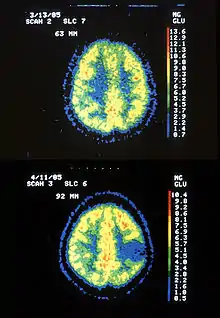

| Two PET images—the upper of which shows a normal brain and the lower shows astrocytoma. | |